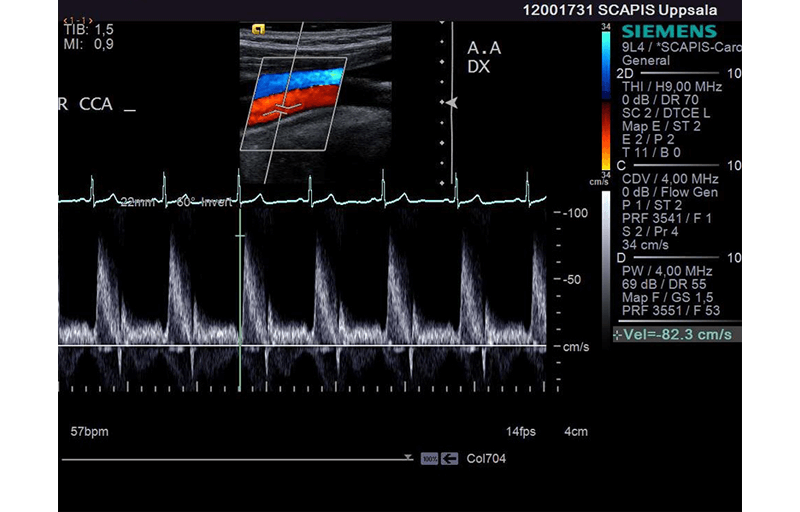

Här har man visat att datorbaserad bildanalys med en ny programvara kan användas för att hitta åderförkalkningsplack med hög risk för både stroke och hjärtinfarkt.

Datoriserad bildanalys av blodkärl i halsen.

Foto: SCAPIS, Hjärt-Lungfonden